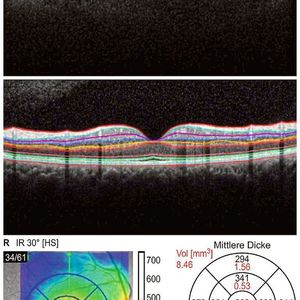

Ob und inwiefern sich auch Veränderungen bei psychiatrischen Erkrankungen wie der Schizophrenie im Auge nachweisen lassen, haben Forscher um den Ulmer Psychiater Professor Carlos Schönfeldt-Lecuona und den Neurologen Professor Elmar Pinkhardt untersucht. Dafür nutzten die Wissenschaftler die Optische Kohärenztomographie (OCT), ein nichtinvasives und dreidimensionales Bildgebungsverfahren aus der Augenheilkunde, mit dem sich Dicke und Volumen der Netzhautschichten schnell, genau und nebenwirkungsfrei bestimmen lässt.

Bei 26 Ulmer PatientInnen mit einer Schizophrenie oder schizoaffektiven Störungen wurden die Netzhautscans durchgeführt und mit einer gesunden Kontrollgruppe verglichen. „Zum ersten Mal haben wir bei Schizophrenie-Patienten und einer in Alter und Geschlecht entsprechenden Kontrollgruppe eine hoch aufgelöste Einzelschichtanalyse der Netzhaut durchgeführt. Um Ungenauigkeiten der Software auszuschließen, wurde die Segmentierung der Netzhautschichten zudem manuell korrigiert“, beschreibt Professor Carlos Schönfeldt-Lecuona von der Universitätsklinik Ulm für Psychiatrie und Psychotherapie III das aufwändige Verfahren.

Die Ergebnisse sind eindeutig: Bei Schizophrenie-Patienten zeigt die Untersuchung eine stark reduzierte Dicke und ein geringeres Volumen fast aller gemessener Netzhautschichten. Im Vergleich zu gesunden Probanden erreichen die Unterschiede eine statistische Signifikanz für Makulavolumen und -dicke sowie für die retinale Nervenfaserschicht und die innere Körnerschicht. Dabei nimmt das Gesamtvolumen der Nervenfaserschicht mit längerer Krankheitsdauer ab.